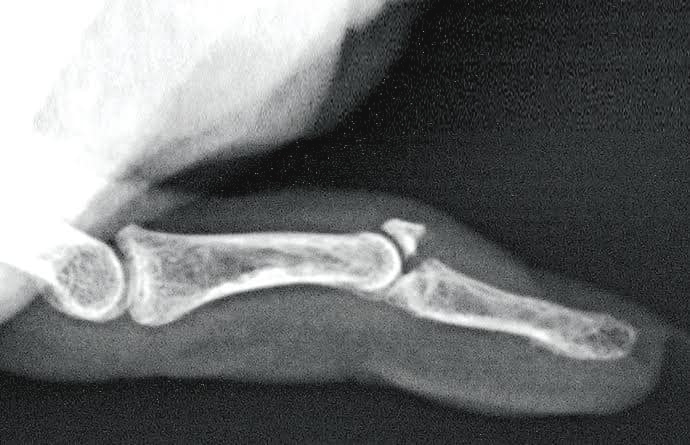

| (圖一) 槌狀指手指末端呈下垂的狀態 | (圖二)槌狀指可分為肌腱斷裂或尾指骨折 |

槌狀指患者手指最尾一節通常呈向下垂的形態(圖一),怎樣用力也不能伸直。這是因為負責伸直手指的肌腱(俗稱筋)不能把最尾一節拉起,主要原因為:

1. 末端指關節骨頭沒有受傷,不過控制該關節伸展功能的肌腱斷裂。(圖二)

2. 關節伸肌腱韌帶沒有受損,不過最尾一節指骨骨折。(圖二)

以上兩種情況都會造成尾指骨關節功能的受損,以致出現受傷消腫之後最尾一節指骨不能伸直。

| (圖三) X光可清晰看到手指有否骨折 | (圖四) 手指固定托 |